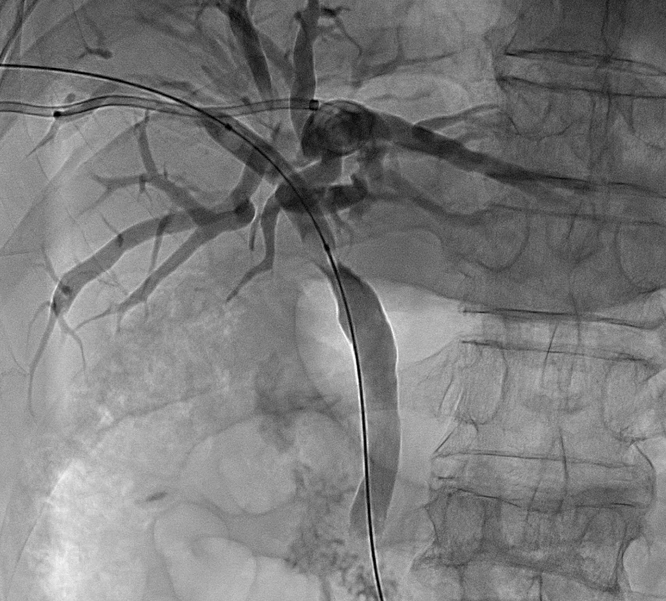

胆道粒子支架是将金属胆道支架与放射性粒子(通常为碘-125,¹²⁵I)相结合的一种创新型介入治疗手段。

金属支架植入后可即刻扩张狭窄的胆道,恢复胆汁引流通畅,迅速缓解黄疸症状。

支架提供即时的胆道再通,放射性粒子则通过持续照射延缓肿瘤向支架腔内生长,两者协同实现更持久的治疗效果。。

将“减黄”(引流)和“抗肿瘤”(粒子)两种治疗合二为一。通常采用三腔结构,包括一个较大的胆汁引流腔和一到两个较小的粒子腔。

将携带粒子的引流管引入狭窄支架内

粒子能量在支架内局部释放,引流的同时,使支架再通